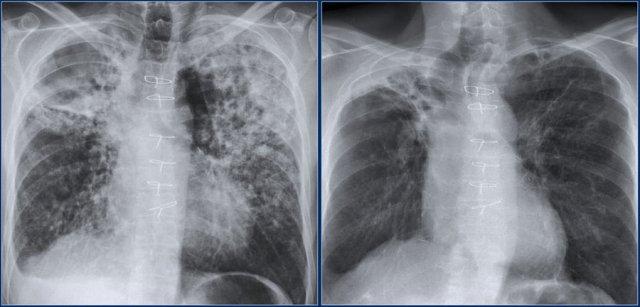

Kiểu hình ảnh dạng lưới trong suy tim sung huyết

Hãy quan sát các hình ảnh rồi tiếp tục đọc.

Các dấu hiệu bao gồm:

- Phim cũ bình thường ở bên trái.

- Kiểu hình ảnh dạng lưới đặc biệt ở vùng đáy phổi. Có thể thấy một số đường Kerley B.

- Tim to.

- Tràn dịch màng phổi bên trái.

- Mạch máu phổi nổi bật hơn so với phim cũ.

Dựa trên các dấu hiệu này, chúng ta có thể kết luận đây là suy tim sung huyết.

Đây là kiểu hình ảnh mô kẽ phổ biến nhất trên phim X-quang ngực thẳng.

Phù mô kẽ thường biểu hiện dưới dạng lưới.

Đôi khi có thể thấy các đường Kerley B.

Đây là một ví dụ khác.

Đường Kerley B là các đường nằm ngang dài 1-2 cm gần màng phổi bên.

Chẩn đoán phân biệt chính của đường Kerley B là:

- Phù mô kẽ trong suy tim

- Viêm bạch mạch do ung thư (lymphangitis carcinomatosa)

Đây là một phim X-quang ngực thẳng khác với phù mô kẽ và đường Kerley B ở bệnh nhân suy tim sung huyết.

CT cho thấy dày vách liên tiểu thùy.

Đôi khi hình ảnh dạng lưới thô hơn như trong trường hợp suy tim sung huyết này.